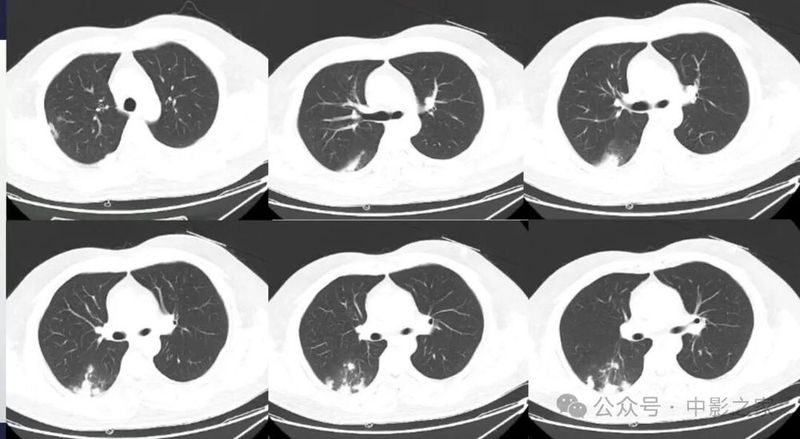

二、浸润实变型

1、分布多为下叶胸膜下

2、实变区密度均匀;

3、大部分病灶与胸膜相连(95%),糊墙征(个别可以栽赃)

4、晕征:大部分有,晕的大小不一致,相对而言实变区密度偏低的晕范围大一些,约20%无晕征;

5、实变区密度均匀或内部有片状低强化(各自占一半左右),且延迟强化;

6、实变区大部分边界清楚,有刀切征、平直征;20%边界稍模糊,30%周围有毛刺征;

7、含气支气管征与密度、晕征的关系:支气管可以直达远端,也可以近端堵塞,堵塞处支气管正常或稍扩张,走形正常;密度密实程度越高晕征越少,含气支气管近端堵塞的几率越高:如果周围晕征明显,密度偏低,边界欠清晰,含气支气管会直达远端;

8、空洞:约50%见到空洞或空腔,内壁光滑,可以多个组成,周围无坏死,内部无液平,可以有残余结构,个别内壁欠光滑;

9、近端均与血管相连。